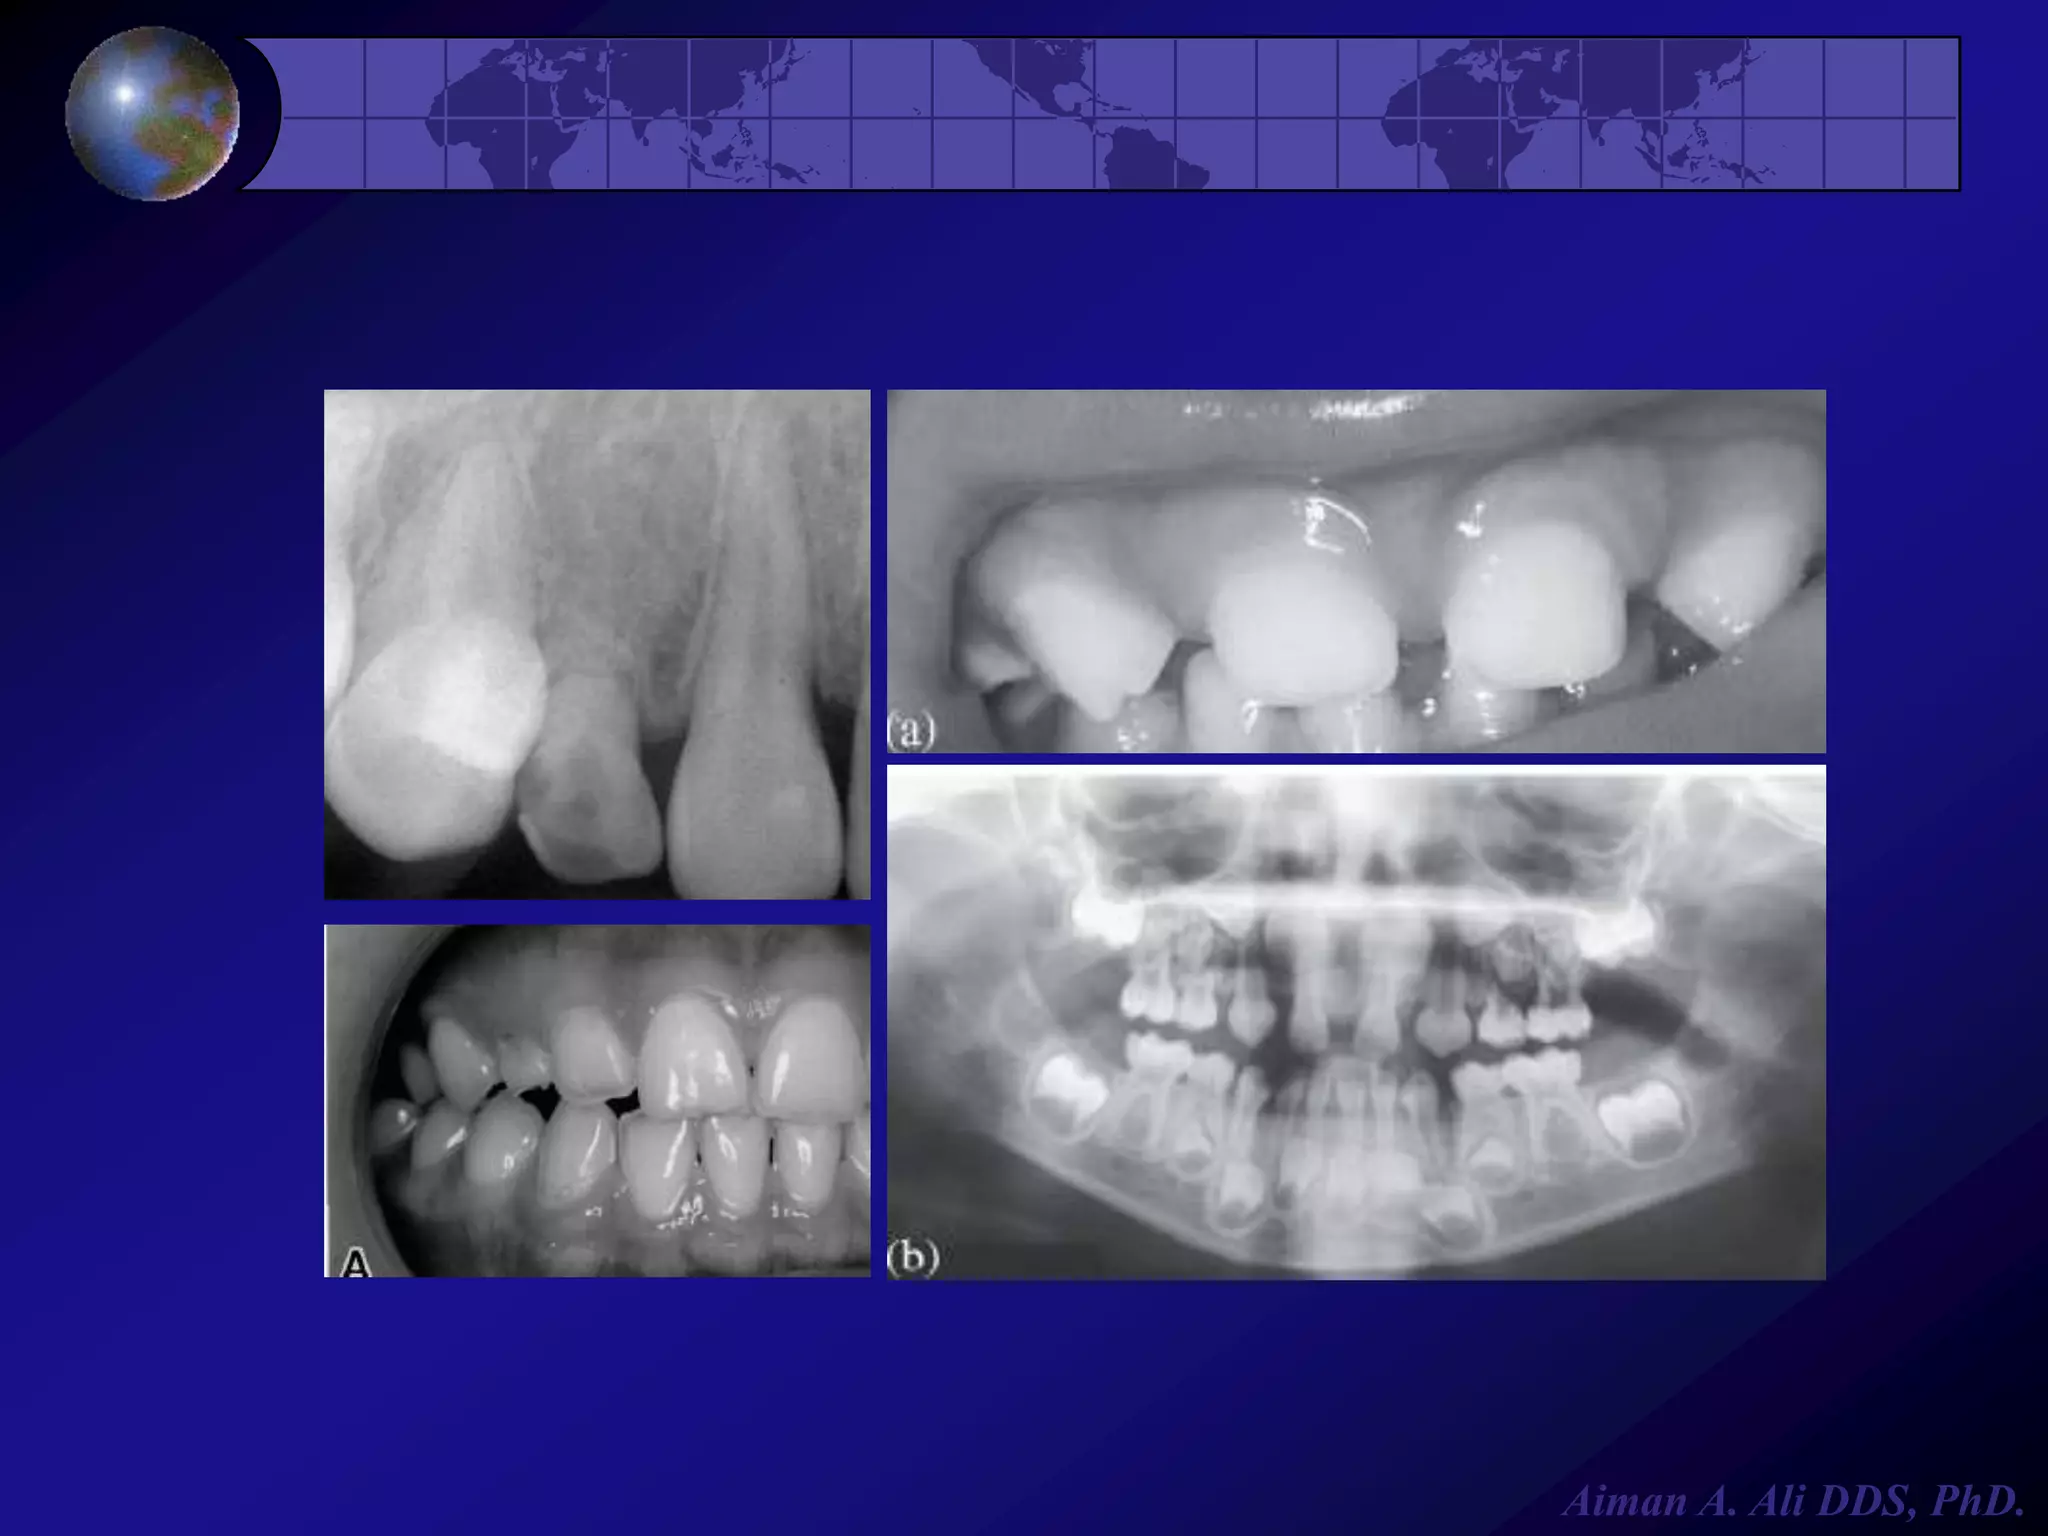

Alterations in Number

Impaction



It is most commonly seen in

mandibular third molars &

maxillary cuspids, it occurs

because of:



Crowding

Physical barrier

Abnormal eruption path

Ankylosis (fusion of tooth to

alveolar bone)

Aiman A. Ali DDS, PhD.